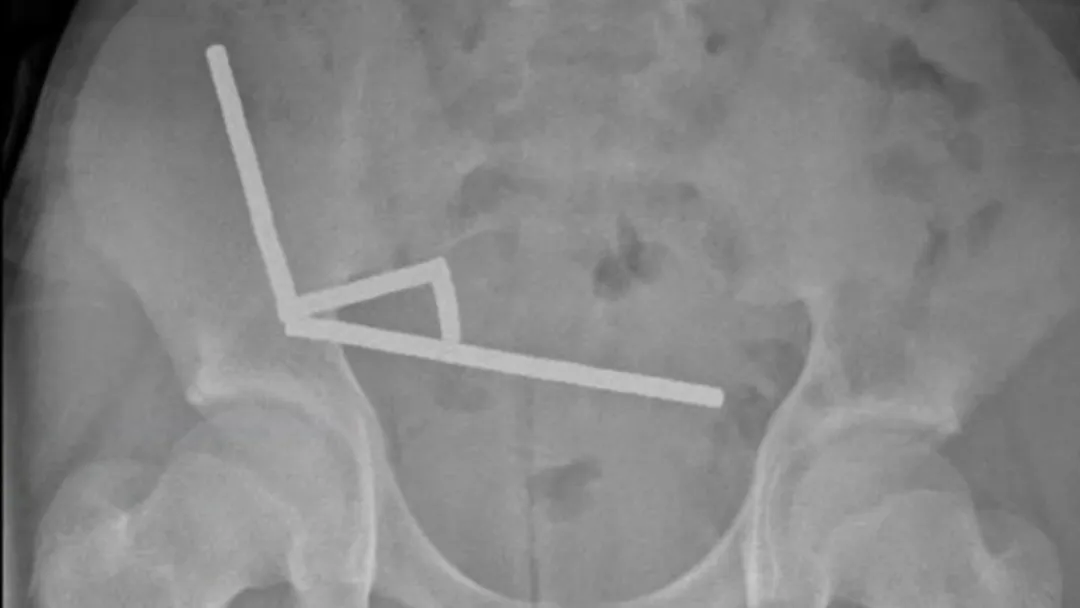

医生通过 X 光片观察到,男孩肠道的不同部位出现了四条线状的磁铁链。

腹部 X 光片显示了磁铁分布情况 来源:Lekamalage et al., NZMJ, 2025